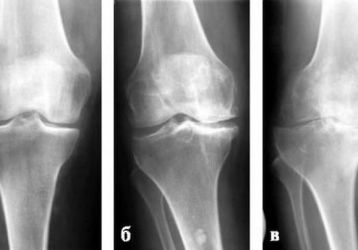

Остеоартроз коленного сустава: причины развития болезни, стадии, симптомы, как лечить недуг

Остеоартроз коленного сустава: причины недуга, люди входящие в группу риска. Характерные симптомы 1,2,3 степени патологии. Методы лечения остеоартроза колена.

Лечение остеоартроза коленного сустава 2 степени, причины и симптомы заболевания

Каковы причины и симптомы остеоартроза 2 степени коленного сустава. Лечение остеоартроза разными способами, почему не стоит лечить заболевание самостоятельно.